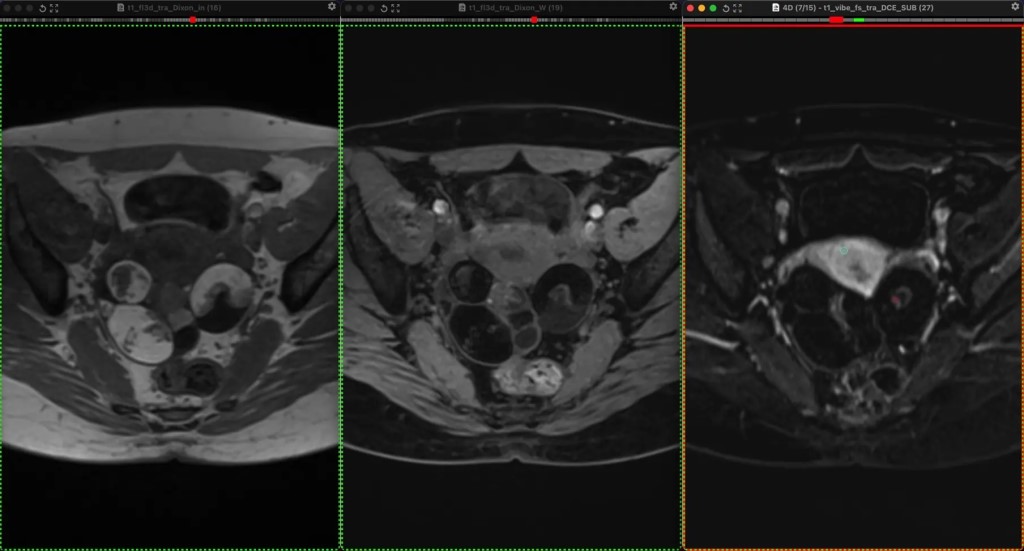

Фото Классные тератомы. 30 лет. В ОРАЦ есть интересный момент: когда речь о тератоме, то надо оценить, есть ли значительное количество ткани, накапливающей контраст. Субъективная вещь. Один сочтёт, что значительное, другой сочтёт, что не значительное. Но в первом случае это будет четвёртая категория и опухоли надо удалять, а во втором случае это будет вторая категория, и можно просто спокойно понаблюдать. Только что переубедил коллегу написать двойку вместо четвёрки по этим картинкам. Кривую показываю на всякий случай, она на присвоение категории в данном случае не влияет, но дополнительно успокаивает, что ли. А зубчатость её объясняется тем, что исходные изображения и изображения после субтракции представляют собой одну серию, а вручную их разделять мне было лень. На информативность кривой это никак не влияет. Видно, что в миометрии контраст накапливается гораздо быстрее и гораздо сильнее. То есть, если бы это на что-то влияло, то эту кривую надо было бы расценить, как кривую низкого риска.